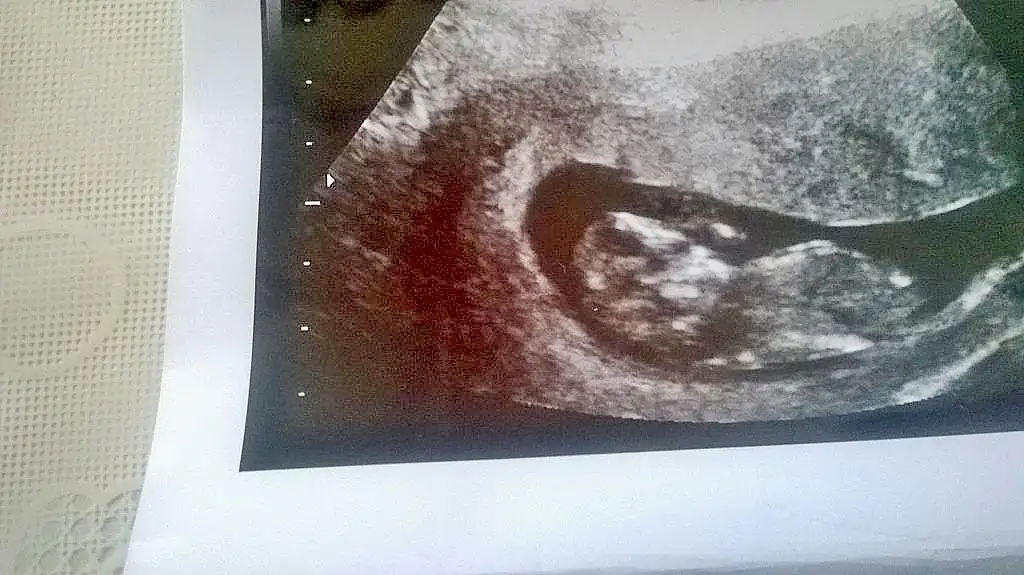

Bu nasıl düzeltme yaptım ama bukadarEki Görüntüle 1515033

Canım bebek çok hareketliydi çok uğraştı ama yok. Goremiiyom dedi.2hafta sonra gidecek tekrar.Eyham canım bebeğin arkası dönük o yüzden görünmüyor nubu doktorun görmemesi normal bir daha ne zaman gideceksin?